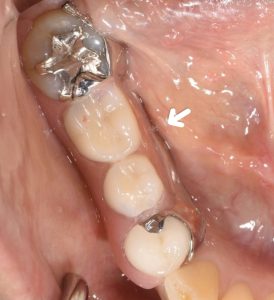

After

ノンクラスプデンチャーとは、入れ歯のバネ部分がピンク色の樹脂でできた入れ歯です。

・金属のバネではなく、ピンク色の樹脂のバネのため、見た目が良い。